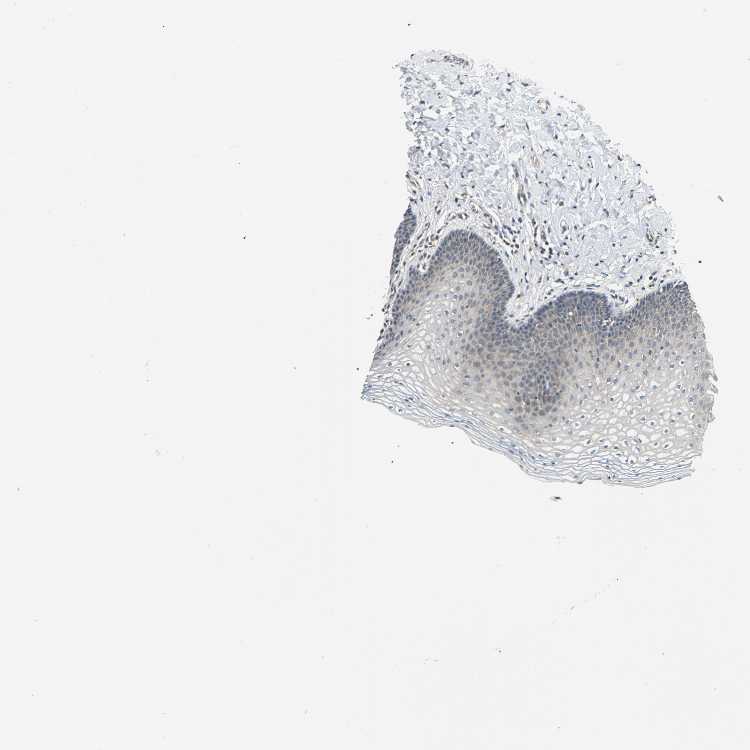

VAGINA - Antibody stainingi

Antibody staining in the annotated cell types in the current human tissue is reported as not detected, low, medium, or high, based on conventional immunohistochemistry profiling in selected tissues. This score is based on the combination of the staining intensity and fraction of stained cells.

Each image is clickable and will lead to virtual microscopy that enables deeper exploration of all samples and also displays staining intensity scores, fraction scores and subcellular localization as well as patient and tissue information for each sample.

Antibody HPA004895Antibody CAB013018

Squamous epithelial cells LowLow